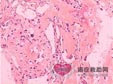

骨肉瘤是恶性增生的棱形间质细胞直接产生的骨样组织或未成熟骨。

骨肉瘤病理变化